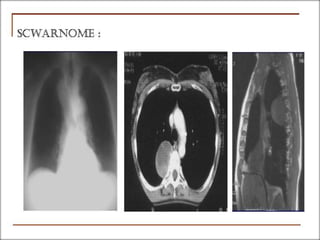

3.1.2- tumeurs du médiastin antero-

inférieur

3.1.2 -1- kystes

pleuropéricardiques

3.1.2- tumeurs du topographique

médiastin antero-inférieur

3.1.2 -1- kystes pleuropéricardiques

 Sont dérivés de récessus clos de la

cavité coelomique et sont bénins.

 Ils sont plus fréquents à droite

rarement à gauche ou post,

 = formations kystiques à parois

tendues, minces, sans adhérence au

poumon, contiennent un liquide (eau de

roche) dont la cytologie ne montre

aucun élément et la chimie est celle

d’un transsudat.

III. Diagnostic

topographique

3.1.2- tumeurs du médiastin antero-inférieur

Clinique souvent asymptomatique.

Rx thoracique:

Echo thoracique:

TDM.:

kyste , contenu liquidien sans

rehaussement apres injection du

produit de contraste.